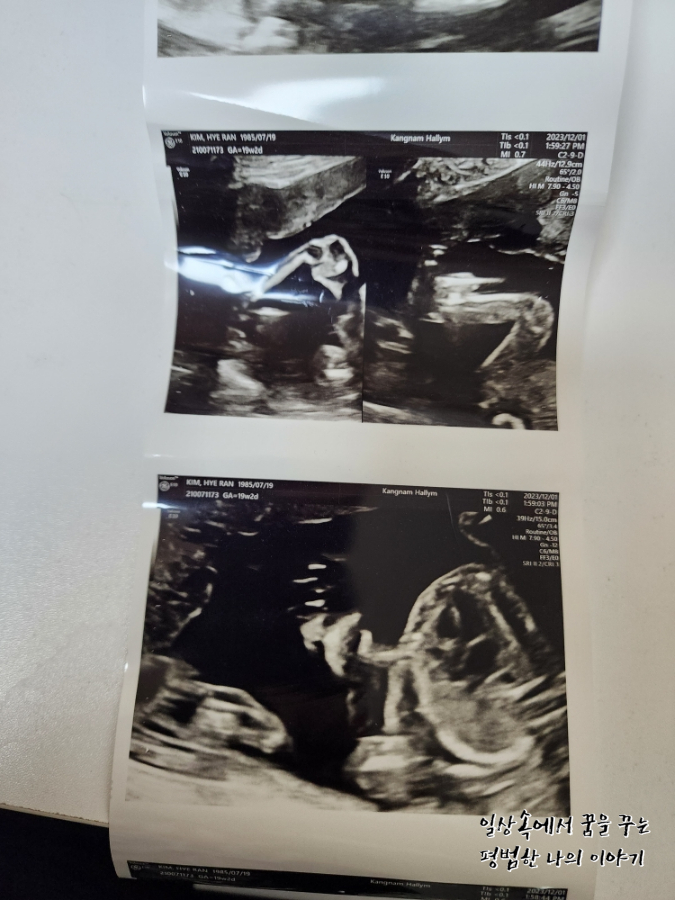

4주 만에 방문한 병원에서 삼등신이 된 아기를 만날 수 있었다. 이번에는 정확한 성별을 들을 수 있지 않을까 내심 기대했는데 아니나 다를까 정확하게 딸이라고 성별을 알려주셨다. 남편은 딸이라는 얘기를 듣자마자 이전부터 생각해뒀던 딸 이름으로 아기를 부르기 시작했다. 태동은 아직 느껴지지 않는데 이안이 때도 좀 늦게 느끼기 시작한 편이라 마음이 조급하지는 않다. 지금 걱정인 건 이안이 때는 임신 후반부터 아래쪽이 뻐근하고 아팠는데 둘째는 그 뻐근함이 너무 빨리 찾아와서 16주 정도 됐을 때부터 오후가 되면 붓기 시작해 서 있는 것조차 힘들어지기 시작했다. 의사 선생님께 괜찮은 거냐고 물어보니 다행히 아기한테는 아무런 영향이 없다고 하셨고 해결할 수 있는 방법은 역시나 출산뿐이라고 하셔서 버티는 수밖에 없겠구나 싶었다. 약간 자궁에 피고임이 있어 걱정이 되었는데 의사 선생님이 무리하지 말라고 하시더라. 자궁 내에 있는 피고임이라 증상이 악화돼도 알 수 있는 방법이 없기 때문에 배가 너무 아프거나 하면 바로 병원으로 오라고 하셨다.